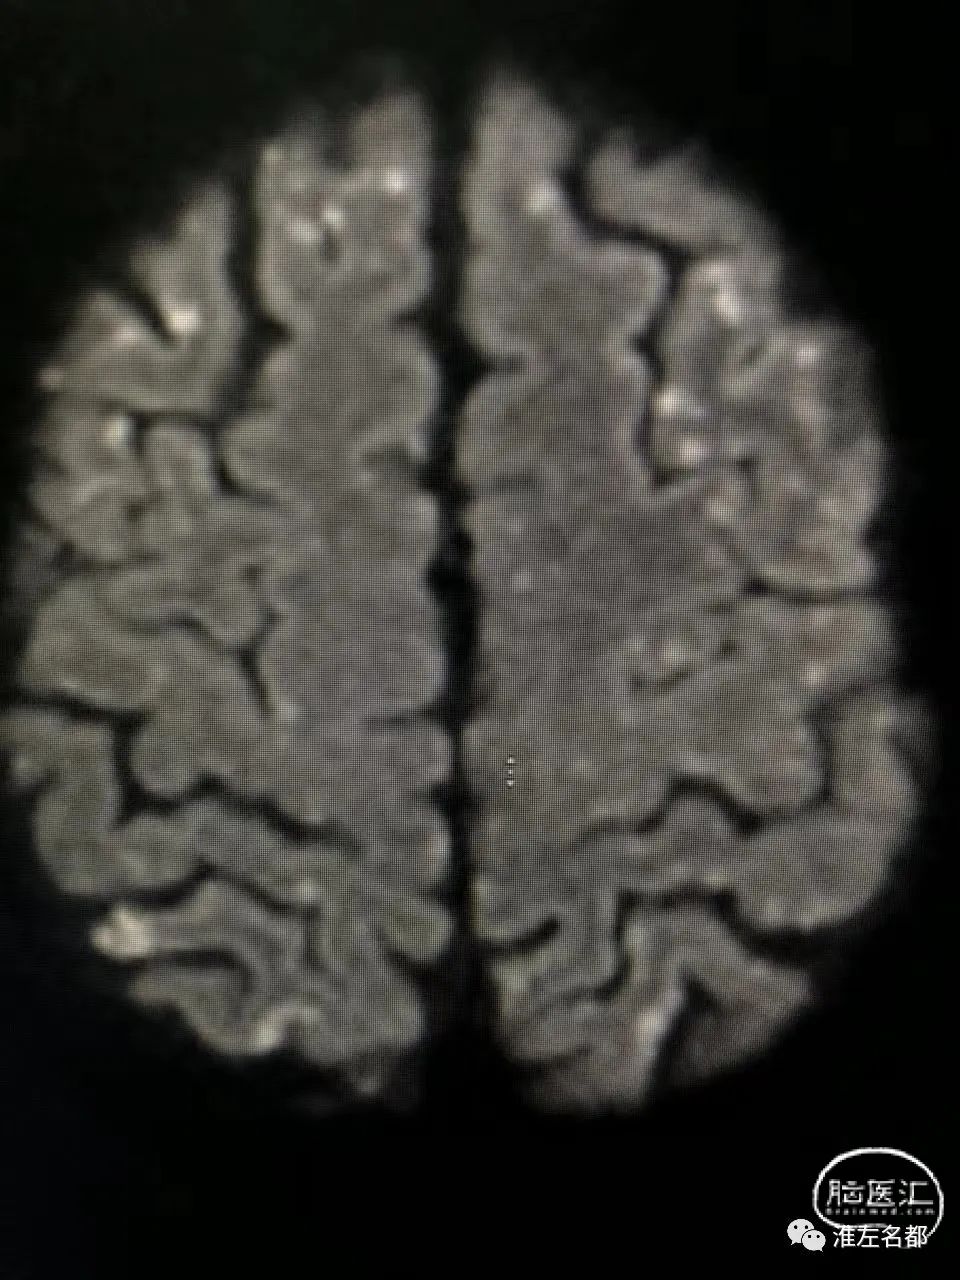

脑DWI:双侧半球皮质和皮质下弥漫分布的点状急性微小梗死灶。